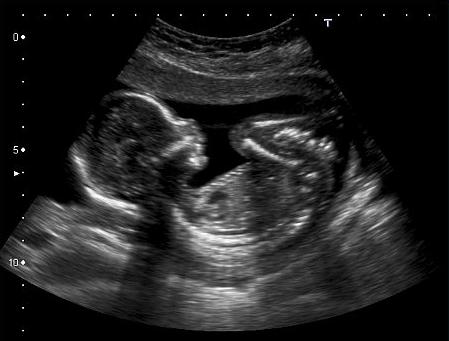

Developing in a tight cocoon

While your mother’s belly is a balloon

A wonderful image of being knit together in my mother’s womb.